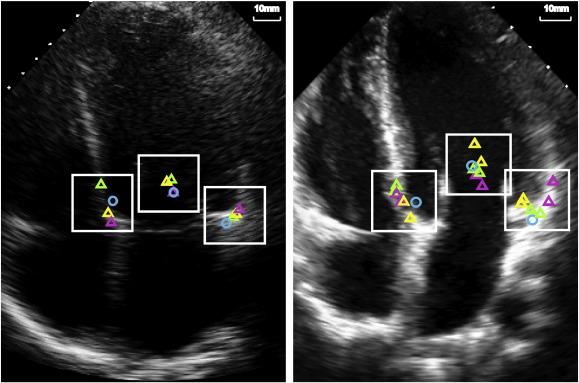

Transmitral pulse wave (PW) Doppler and annular tissue Doppler velocity measurements provide valuable diagnostic and prognostic information. However, they depend on an echocardiographer manually selecting positions to make the measurements. This is time-consuming and open to variability, especially by less experienced operators. We present a new, automated method to select consistent Doppler velocity sites to measure blood flow and muscle function.

Our automated algorithm combines speckle tracking and colour flow mapping to locate the septal and lateral mitral valve annuli (to measure peak early diastolic velocity, E') and the mitral valve inflow (to measure peak inflow velocity, E). We also automate peak velocity measurements from resulting PW Doppler traces. The algorithm-selected locations and time taken to identify them were compared against a panel of echo specialists - the current "gold standard".

The algorithm identified positions to measure Doppler velocities within 3.6 ± 2.2mm (mitral inflow), 3.2 ± 1.8mm (septal annulus) and 3.8 ± 1.5mm (lateral annulus) of the consensus of 3 specialists. This was less than the average 4mm fidelity with which the specialists could themselves identify the points. The automated algorithm could potentially reduce the time taken to make these measurements by 60 ± 15%.

我们的自动算法结合了斑点追踪和彩色血流图,以定位隔瓣和侧瓣二尖瓣环(测量早期舒张峰值速度 E')和二尖瓣流入(测量峰值流入速度 E)。我们还自动测量 PW 多谱勒迹线的峰值速度。将算法选择的位置和识别这些位置所需的时间与一组超声专家进行了比较,这是目前的“黄金标准”。

该算法在 3.6±2.2mm(二尖瓣流入)、3.2±1.8mm(隔瓣环)和 3.8±1.5mm(侧瓣环)的范围内确定了测量多谱勒速度的位置,这比专家们自己能够识别这些点的平均 4mm 精度要小。该自动算法有可能将完成这些测量的时间减少 60±15%。